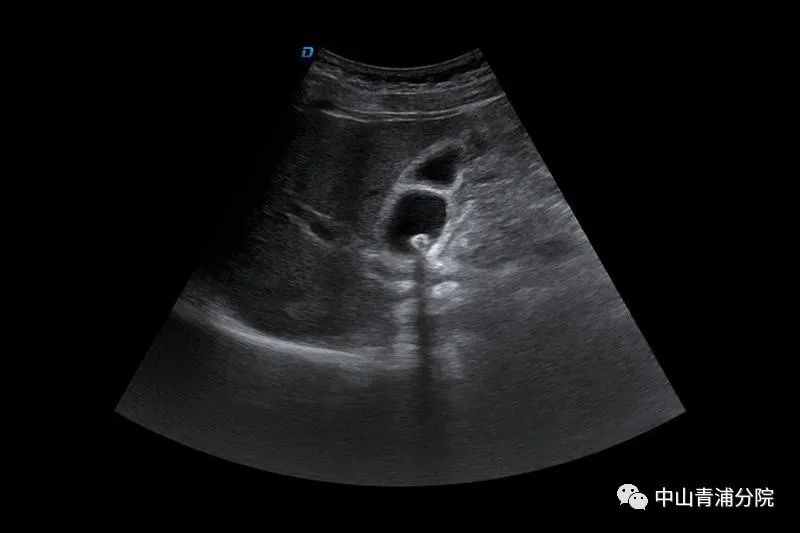

(胆囊结石B超表现)

患者往往有胆绞痛发作的病史,发作部位多位于上腹部或右上腹部,一般持续15分钟以上,疼痛可放射至右肩或后背,常伴有恶心或呕吐。大多数胆囊结石可以通过腹部B超、CT、内镜超声或磁共振胰胆管成像(MRCP)等明确诊断。